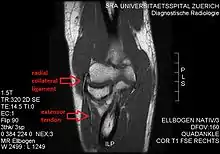

Radial collateral ligament of elbow joint

The radial collateral ligament (RCL), lateral collateral ligament (LCL), or external lateral ligament[Explain 1] is a ligament in the elbow on the side of the radius.